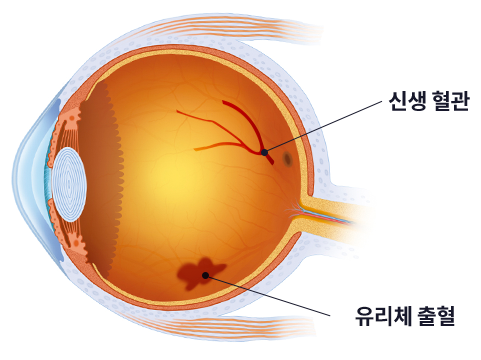

망막혈관이 폐쇄 및 손상됨에 따라 신생혈관이 망막에서 유리체를 향해

자라게 합니다. 신생혈관은 약해서 쉽게 터지고 혈액이 누출될 수 있으며,

섬유 조직과 함께 자라난 신생혈관이 수축하여 망막박리 현상이 나타날 수 있습니다.